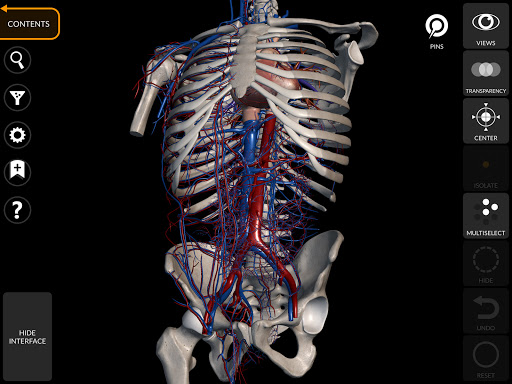

"Anatomy 3D Atlas" memungkinkan Anda mempelajari anatomi manusia dengan cara yang mudah dan interaktif.

Melalui antarmuka yang sederhana dan intuitif, Anda dapat mengamati setiap struktur anatomi dari sudut mana pun.

Model 3D anatomi sangat terperinci dan memiliki tekstur hingga resolusi 4k.

Pembagian berdasarkan wilayah dan tampilan yang telah ditetapkan sebelumnya memudahkan pengamatan dan studi bagian tunggal atau kelompok sistem dan hubungan antara organ yang berbeda.

MODEL ANATOMI 3D

• Sistem muskuloskeletal

• Sistem kardiovaskular • Sistem

saraf • Sistem pernapasan • Sistem pencernaan • Sistem urogenital (pria dan wanita) • Sistem endokrin • Sistem limfatik • Sistem mata dan telinga FITUR • Antarmuka yang sederhana dan intuitif • Putar dan perbesar setiap model dalam ruang 3D • Opsi untuk menyembunyikan atau mengisolasi satu atau beberapa model yang dipilih • Filter untuk menyembunyikan atau menampilkan setiap sistem • Fungsi pencarian untuk menemukan setiap bagian anatomi dengan mudah • Fungsi penanda untuk menyimpan tampilan khusus • Rotasi cerdas yang menggerakkan pusat rotasi secara otomatis • Fungsi transparansi • Visualisasi otot melalui tingkat lapisan dari yang superfisial hingga yang terdalam • Dengan memilih model atau pin, istilah anatomi terkait akan muncul • Deskripsi otot: asal, • Tampilkan/ Sembunyikan antarmuka UI (sangat berguna dengan layar kecil) MULTIBAHASA • Istilah anatomi dan antarmuka pengguna tersedia dalam 11 bahasa: Latin, Inggris, Prancis, Jerman, Italia, Portugis, Turki, Rusia, Spanyol, Mandarin, Jepang, dan Korea • Istilah anatomi dapat ditampilkan dalam dua bahasa secara bersamaan PERSYARATAN SISTEM • Android 8.0 atau yang lebih baru, perangkat dengan RAM minimal 3GB Reversi